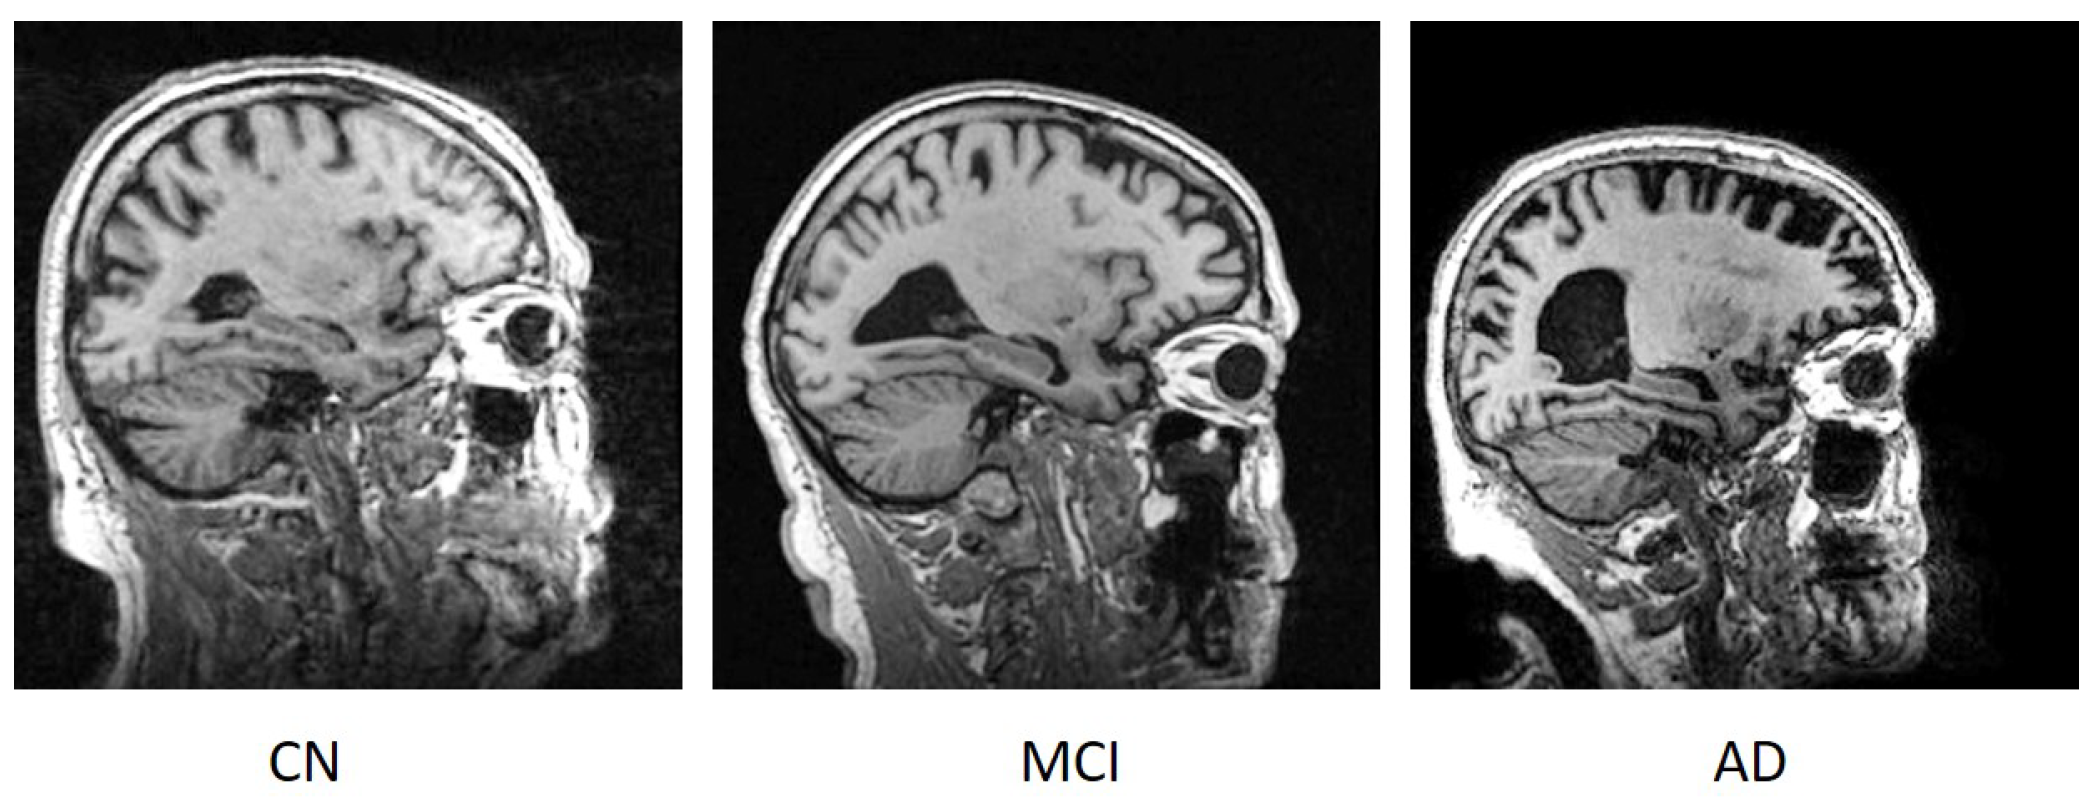

Magnetic resonance imaging (MRI) is a widely used technique for obtaining tissue-by-tissue details about the nervous system [16]. MRI is often used to successfully diagnose a variety of disorders, including cancer, tumours, and others [17]. The discrepancy in brain cells between AD, MCI, and cognitively normal (CN) individuals can be determined with appropriate image processing tools. The traditional AD diagnosing system includes a variety of tests such as physical examination, memory test, genetic information, etc. The utilization of brain images for AD classification may take lesser time than the traditional diagnosing system and needs fewer instruments. Furthermore, optimal brain image processing may reveal significant bio-markers long before a person develops Alzheimer’s disease [18]. Traditional image processing tools, on the other hand, fail to diagnose AD by examining tissue changes due to the intricate pixel formations [19]. Figure 1 shows sample brain MR images for patients with CN, MCI, and AD.

Figure 1.

Sample brain MR image of a CN, MCI, and AD patient.

From Figure 1, it can be observed that the hippocampus region (in the centre of the brain images) in AD patients is much smaller than in CN and MCI individuals. Similarly, the hippocampal size of MCI patients is smaller than that of CN patients.